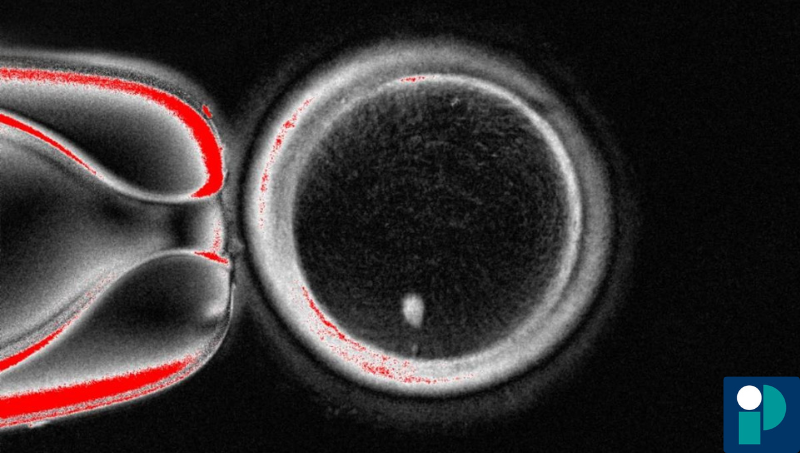

- Se extrae el núcleo de la célula donante y se trasplanta a un óvulo donado que ha sido previamente desprovisto de su propio núcleo (un “óvulo enucleado”).

- Se induce al óvulo reconstituido a realizar una división celular reductiva directa, sin duplicar nuevamente todo el ADN, de modo que se elimine aproximadamente la mitad de los cromosomas (como ocurre naturalmente en la meiosis) — ese paso es lo que llaman “mitomeiosis”.